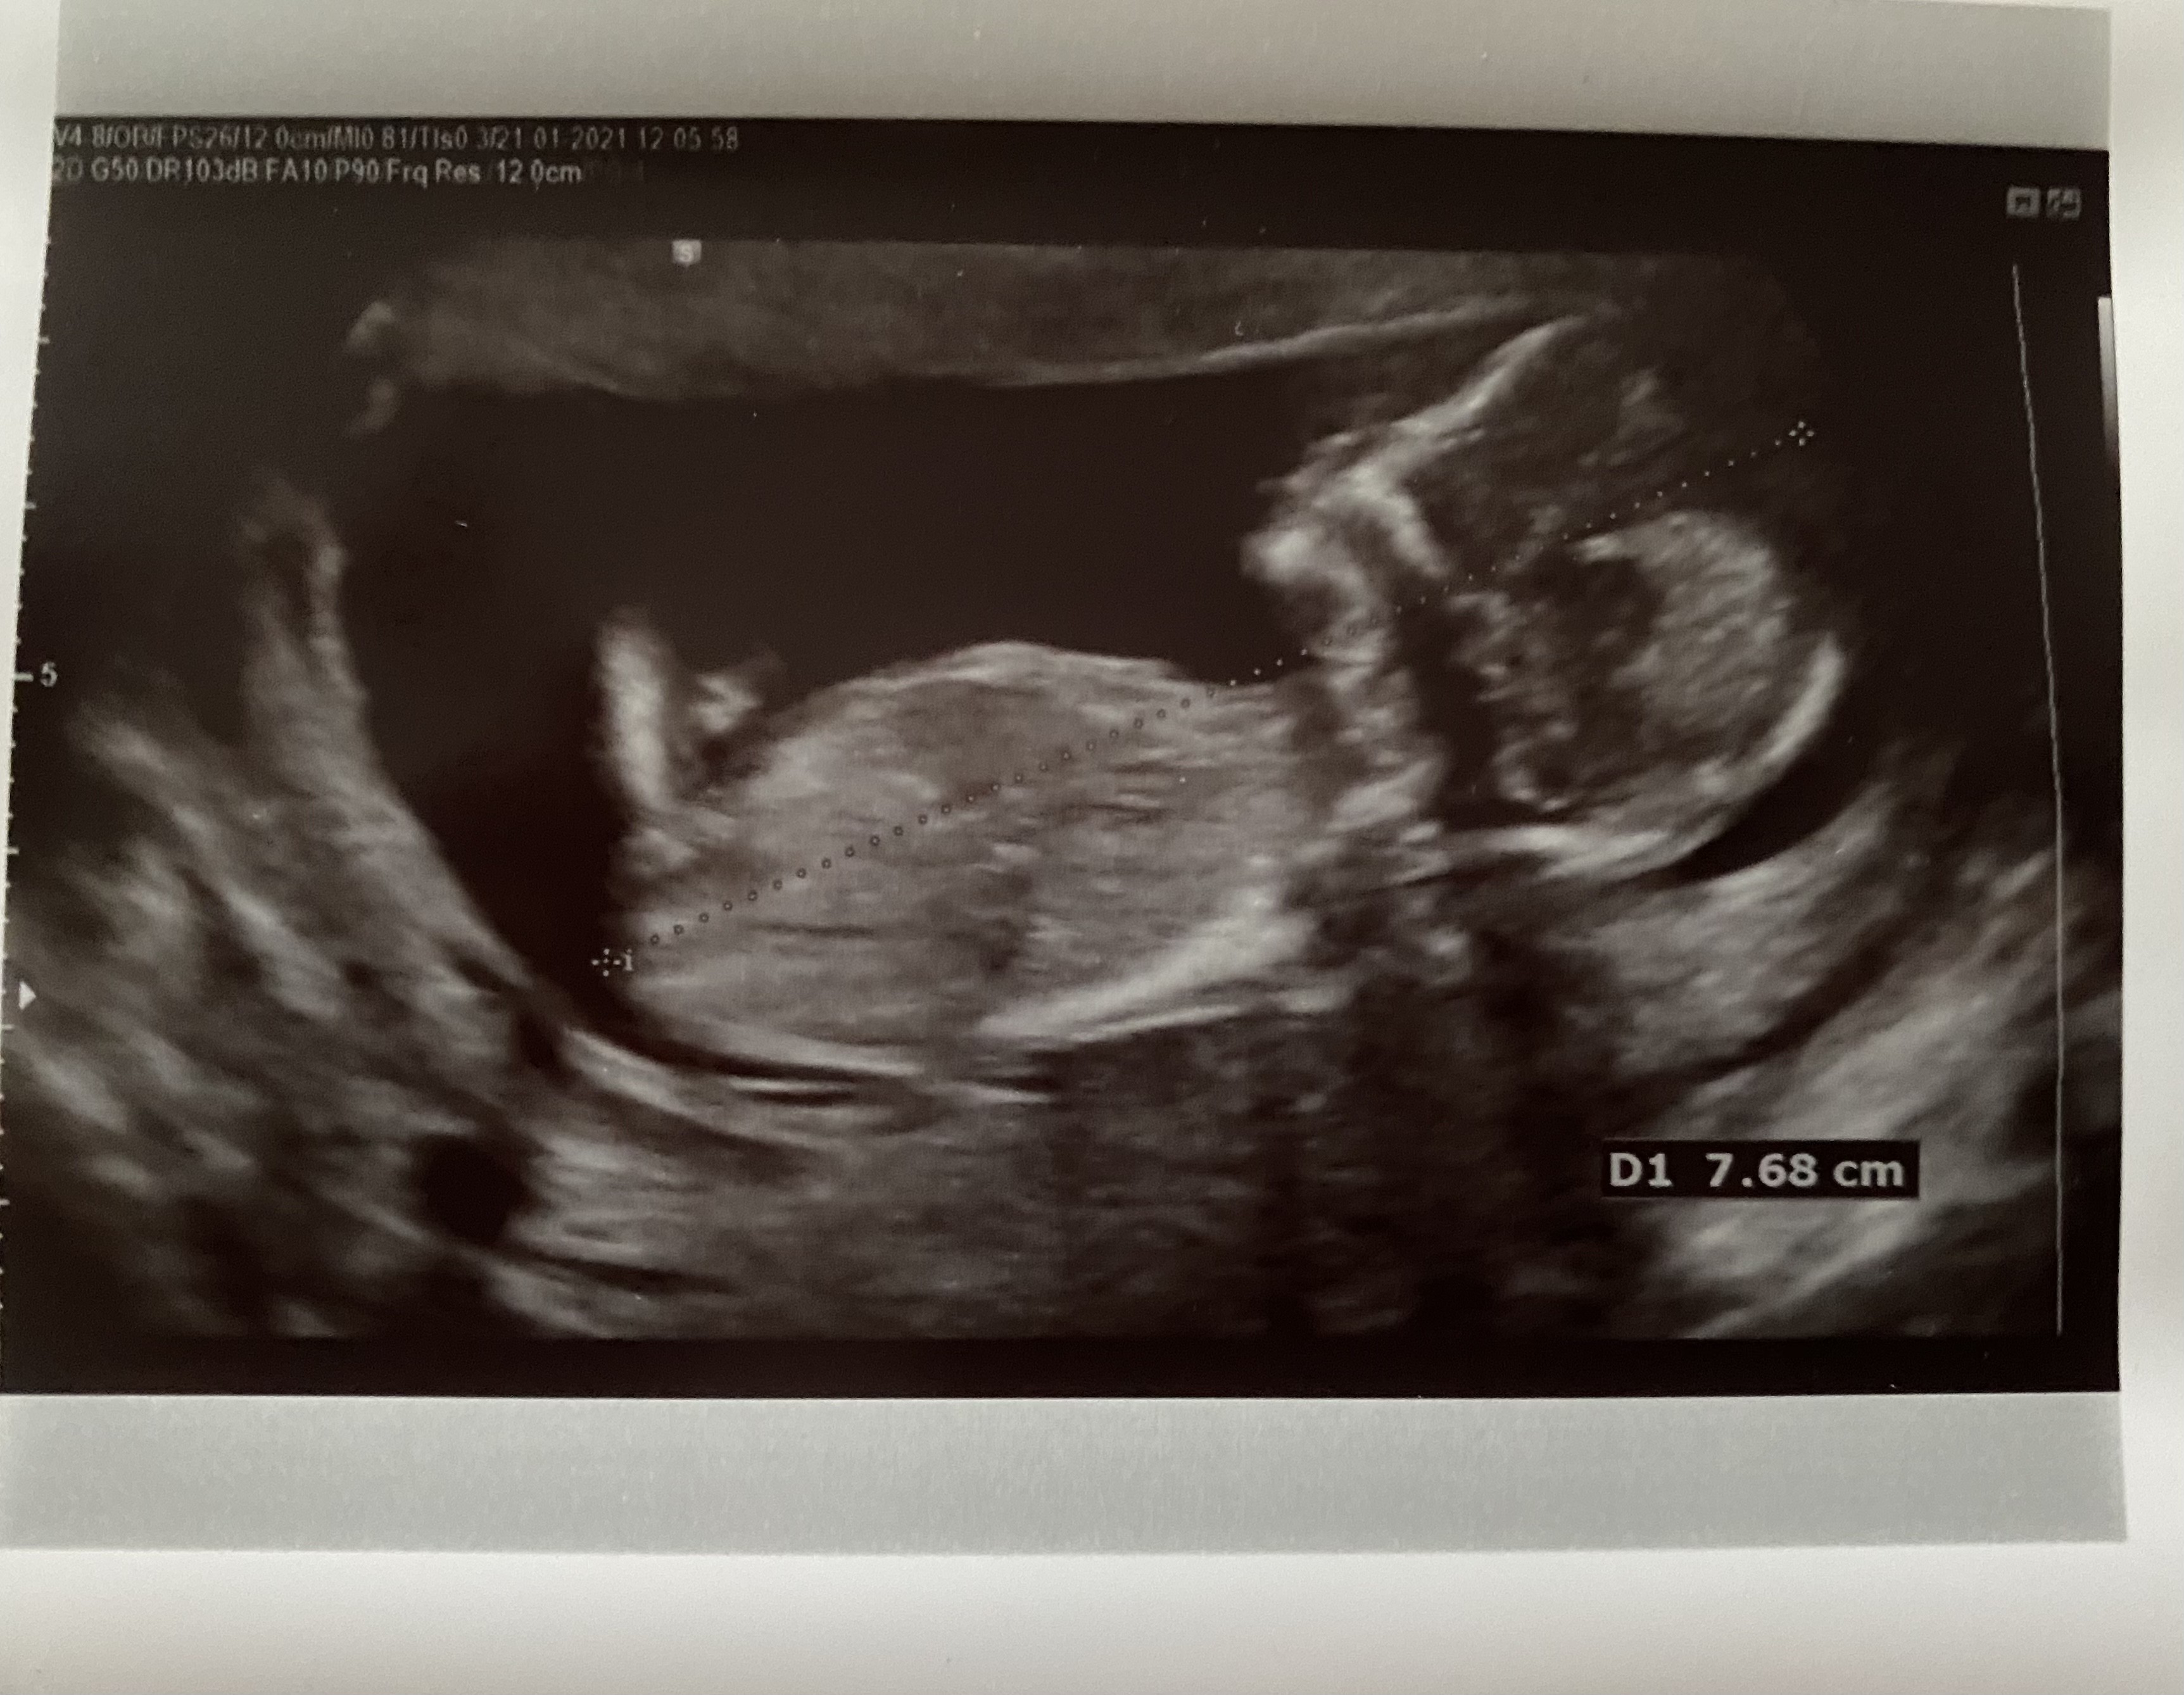

Po sobie samej wiem że nic nie jest na 100% mi w 12 tv na badaniu prenatalnym powiedział lekarz , że 80% dziewczynka , w 14 tc zobaczyłam z moją panią doktor pięknego siusiaka i ja go widziałam na własne oczy , a że moim pierwszym dzieckiem jest synek więc już wcześniej napatrzyłam się jak wygląda siusiak wiec rozczarowanie było po tych 80% , a tu nagle w 17 tc siusiaka brak

i jednak dziewczynka , lekarka mówiła że każde dziecko posiada wlasnei ten wyrostek na samym początku później u dziewczynek on zanika i albo mojej zanikł bardzo późno , albo ten siusiak który widziałyśmy był pępowiną

także dopiero przy porodzie jak zagadnęłam między nogi dziecka byłam pewna co to tam jest albo czego nie ma